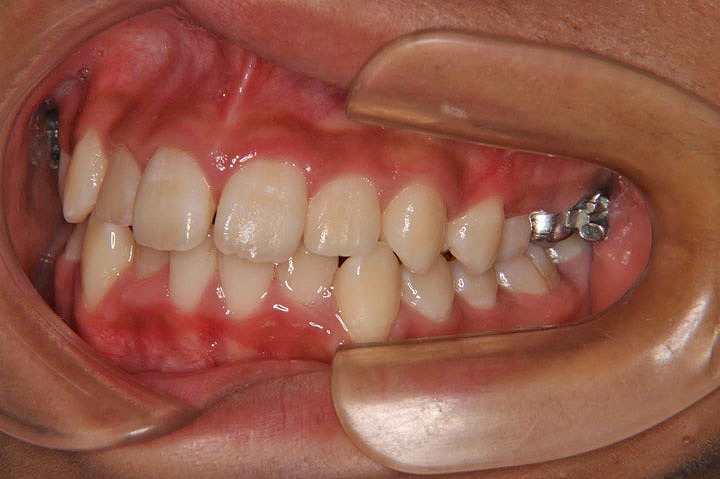

上下の歯のデコボコを主訴に来院された中学校一年生の患者さんです。上顎をクオードヘリックスで、下顎をバイヘリックスで拡大を行い、非抜歯でエッジワイズ装置を用いて配列を行いました。

動的治療中